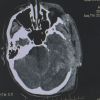

Куля пройшла під оком та вилетіла через скроневу кістку. Із таким важким пораненням ввечері 11 вересня до обласної лікарні імені Мечникова доставили АТОвця.

Аби врятувати хлопцеві життя, медики перелили більш ніж літр крові та зробили складну операцію. Пораненому військовому 24 роки, він – старший сержант.

Лікарі припускають, такі травми – наслідок вогнепального снайперського поранення.